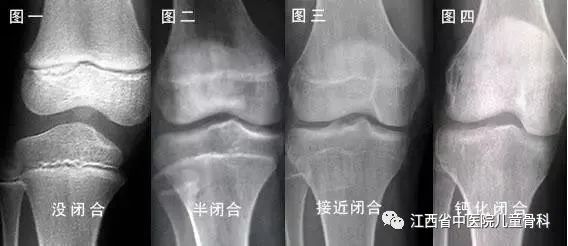

孩子16岁了,还能不能长高,拍摄膝关节X线片就知道了。

如果骨骺还没有闭合,可以充分利用人体骨骺发育的最后阶段,刺激骨骺发育是有可能再长高一些的。如果骨骺已闭合,生长也就停止了。